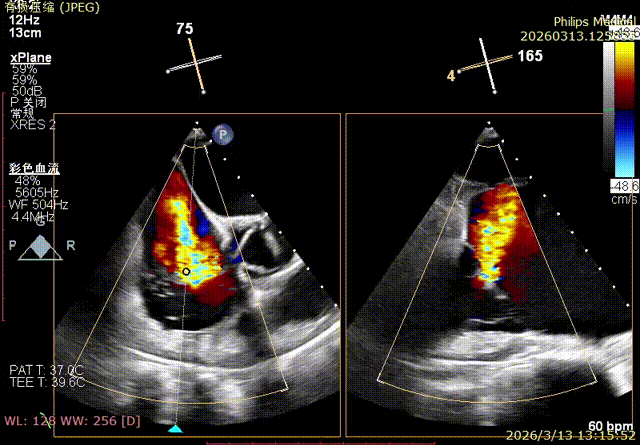

Comparison of Regurgitation Before and After Surgery

Baseline preoperative regurgitation

Postoperative regurgitation baseline

Following annuloplasty, leaflet coaptation was improved compared with the preoperative state, and regurgitation was reduced from severe to trivial.